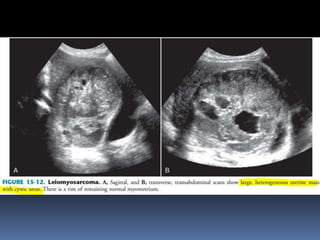

This document contains an image gallery from Dr. Mohit Goel showing various uterine anomalies and ovarian cysts. It includes images of an arcuate and unicornuate uterus, endometritis, a twisted ovarian pedicle, dermoid cysts of varying sizes and echogenicity containing hair, fat, and calcifications, and a combination dermoid cyst showing both mesh and plug structures. The gallery provides ultrasound images of different gynecological conditions for medical education and reference.